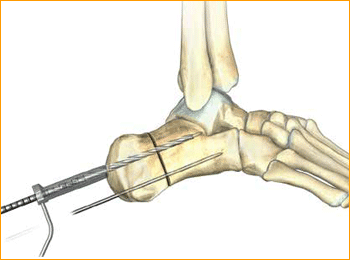

8. FRACTURE COMPRESSION

In order to account for countersinking and fracture compression, a screw that measures 5 mm shorter than the measured total depth is inserted over the guide wire while protecting the soft tissues with a soft tissue guide.

9. SCREW INSERTION

The screw is placed while under fluoroscopic guidance in order to avoid cortical penetration. Postoperative protocol: The patient is placed into a soft dressing, supported by a fiberglass splint. Patients can be made non-weight-bearing for a period of 2–6 weeks postoperatively depending upon Torg type of fracture, bone quality, and underlying morbidities.